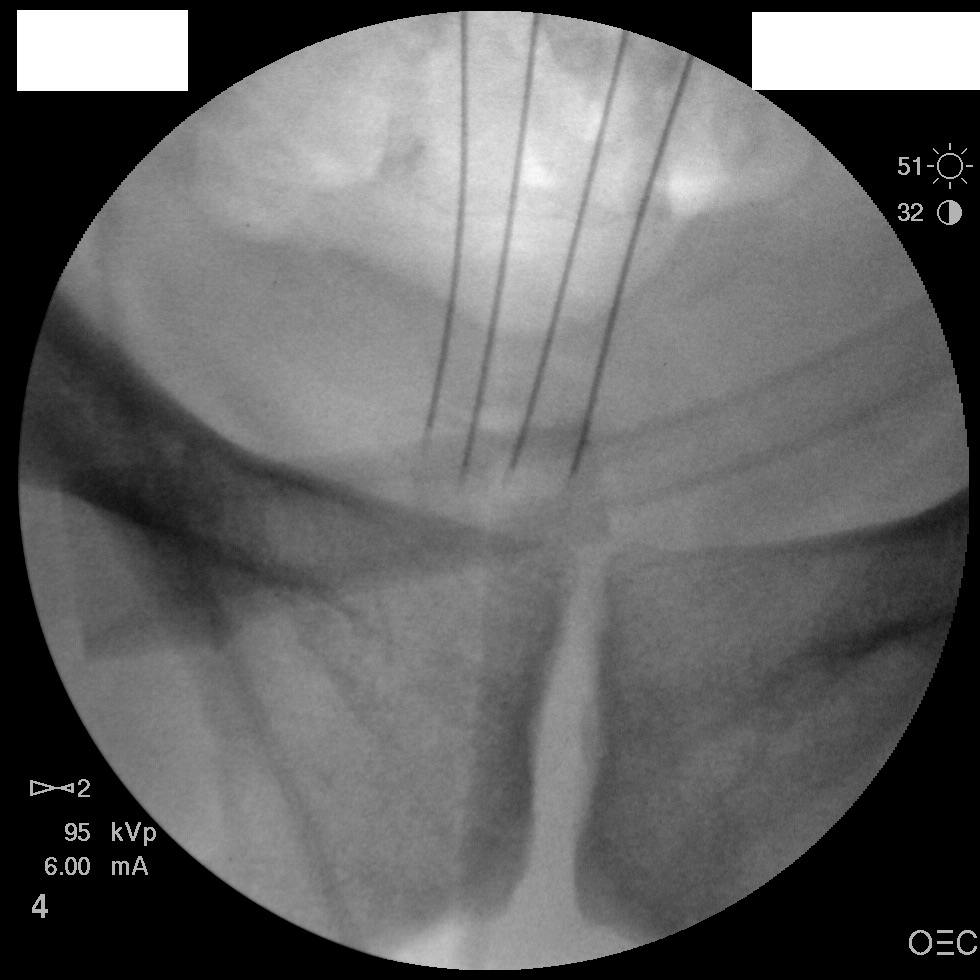

I have a patient with several months of coccyx pain. Worse with sitting, TTP over coccyx. Otherwise normal exam. No trauma, but she has an anteriorly displaced coccyx. Failed NSAIDs and no one around me does good pelvic floor PT. I scheduled her for ganglion impar injection, but her insurance won't pay for it. They wouldn't even let me to a peer-to-peer... they just straight up said they won't cover it. Any other treatment options? I don't want to send her to a surgeon. Thanks.